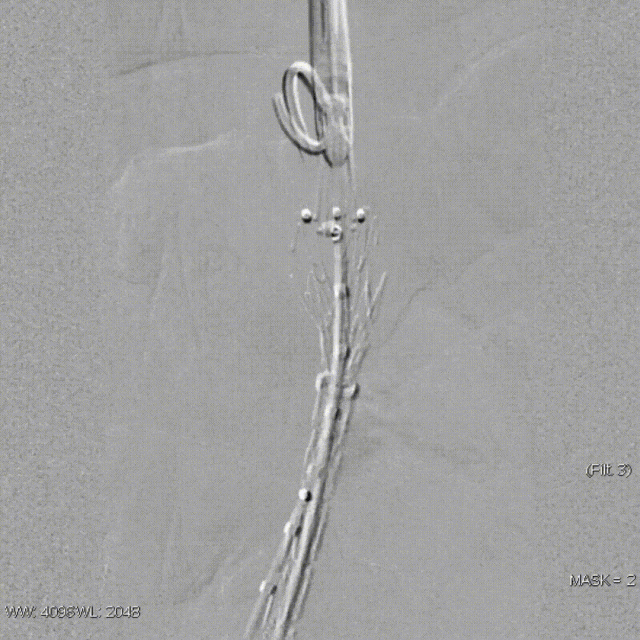

该技术主要适用于采用旋转式释放机制的支架。其核心操作步骤为:在主体支架释放出前2-3节后,轻微松开支架,然后反复反向旋转并上推输送鞘。 这一动作能促使已释放的近端支架段在瘤颈处产生可控的“堆叠”效应,从而更好地顺应瘤颈的弯曲形态,尤其是在大弯侧实现更紧密的贴壁,有效拓展了功能性密封区。

案例二(短瘤颈+梯形瘤颈):患者近端瘤颈长度不足1cm,且伴有大量附壁血栓。选用适当oversize的支架,结合Reverse技术释放,支架主体自动“寻找”并适应最佳的贴附区域,最终造影显示无明确内漏。